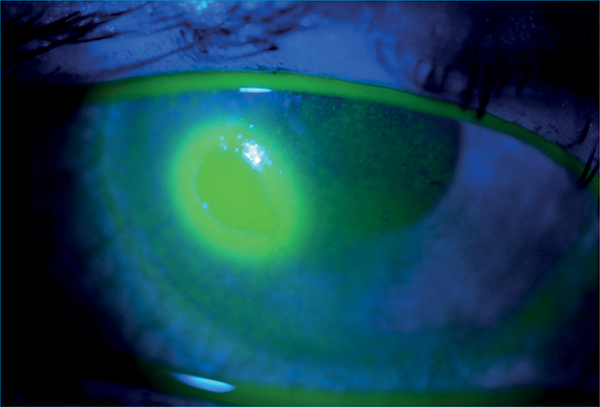

A jelátvitelben a kalciumcsatornáké a főszerep, amelyet a kromoglikátok gátolni képesek. Az ilyenkor legnagyobb mennyiségben felszabaduló mediátor a hisztamin és leukotriének, amelyek az erek tágulatát és fokozott áteresztő képességét okozzák. A vörösség, és a duzzanat mellett (1. ábra) a viszketés az allergia kardinális tünete, amelyet az idegvégződések környezetében felszabaduló hisztamin H1-receptorhoz kötődése okoz.

Könnyfilm-diagnosztika